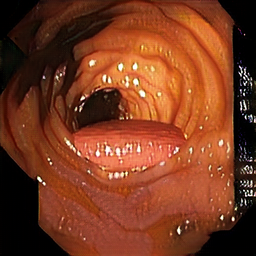

Train data: Synth-colon

• 828 images

• 256x256 pixels

• Generated with Blender

Enric Moreu, Kevin McGuinness, and Noel E O’Connor. “Synthetic Data for Unsupervised Polyp Segmentation”. In: Irish Conference on Artificial Intelligence and Cognitive Science (AICS). 2021.